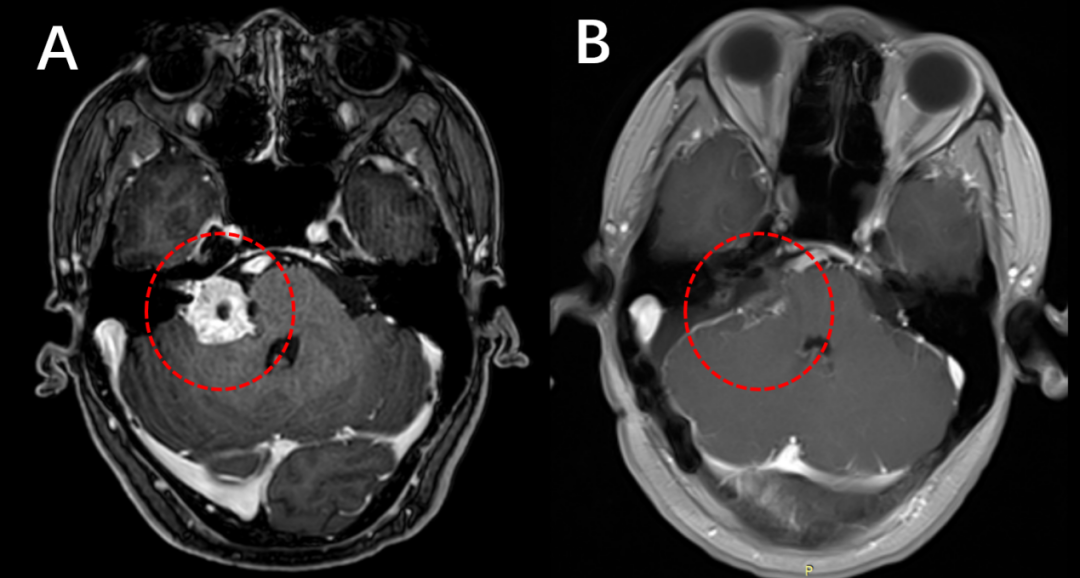

术前(左)和术后(右)增强磁共振检查,对比提示肿瘤完全切除(红色圈内的肿瘤消失)